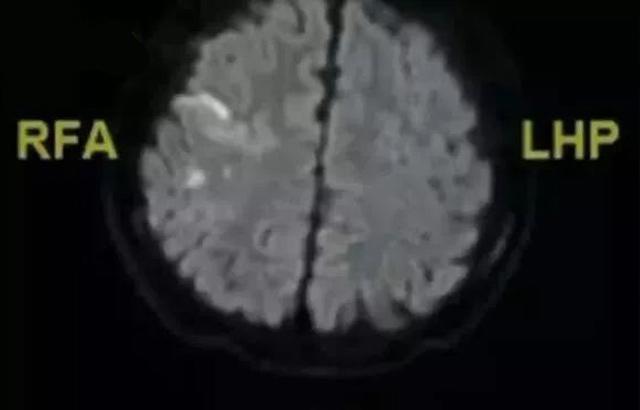

Sau khi kiểm tra, các bác sĩ nhận định cậu bé bị nhồi máu não và đây là lần đầu tiên bệnh viện có trường hợp bị nhồi máu não khi còn rất trẻ.